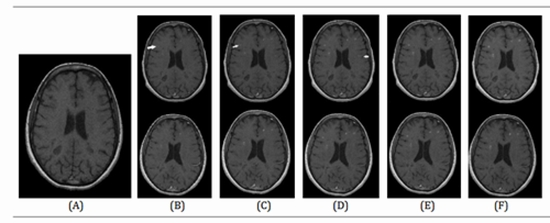

Comparison of Gadovist and Magnevist in Brain Magnetic Resonance Imaging of Multiple Sclerosis Patients with an Acute Attack

Background: The use of an appropriate contrast agent performs a major role in brain Magnetic resonance imaging (MRI) of Multiple sclerosis (MS) patients. Objectives: The present study aimed to make a comparison between the diagnostic values of Gadovist and Magnevist considering the successive imaging times in contrast-enhanced brain MRI of MS patients. Methods: A total of 62 relapsing-remitting MS patients (56 females, mean age of 31 years) were enrolled in the present study. All of them underwent two sessions of standard contrast-enhanced brain MRI upon enrollment and 48 h later. The participants were randomly assigned to each contrast agent. T1-weighted (T1W) images were taken 30 sec, as well as 5, 10, 15, and 30 min after the contrast injection. For all of the images, two neuro-radiologists who were blinded to the contrast type counted the number of plaques in the brain. In addition, for the enhanced plaques larger than 10 mm, the signal intensity (SI) was determined using its region of interest. Results: The mean plaque number significantly increased from 30 sec to 15 min for both contrasts separately (P<0. 001). Nonetheless, the slight increases in the mean plaque number from 15-30 min for both Gadovist and Magnevist were not statistically significant (both PValues>0. 25). The mean plaque number in the Gadovist group was higher, compared to that in the Magnevist group at both 15 and 30 min, and the differences were statistically on the borderline (both P-Values=0. 07). The mean SI of enhanced plaques gradually increased in the course of imaging in both contrast groups. Except for 30 sec, in all other time sessions, the mean SI was higher in Gadovistenhanced MR images, compared to Magnevist-enhanced MR images (P<0. 01). Conclusion: As evidenced by the obtained results, Gadovist showed a relatively better diagnostic value for brain MRI of MS patients. Furthermore, the findings suggested that it is cost-effective to take MRI only up to 15 min (instead of 30 min) after contrast injection in both agents